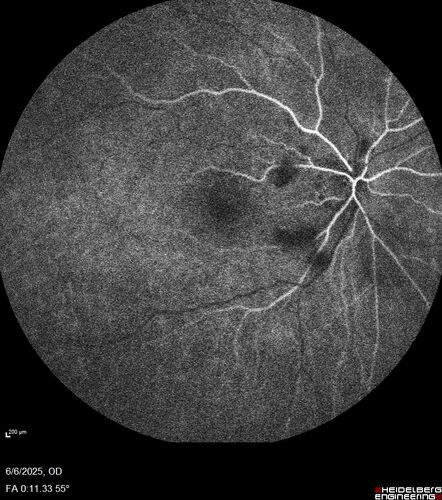

Cotton Wool Spots following cardio-pulmonary bypass

The patient had emergency thoracotomy about 3 weeks ago he had an aortic dissection with a root aneurysm. It had dissected down to the iliacs. The patient had a thoracotomy and aortic valve replacement and large aortic graft.